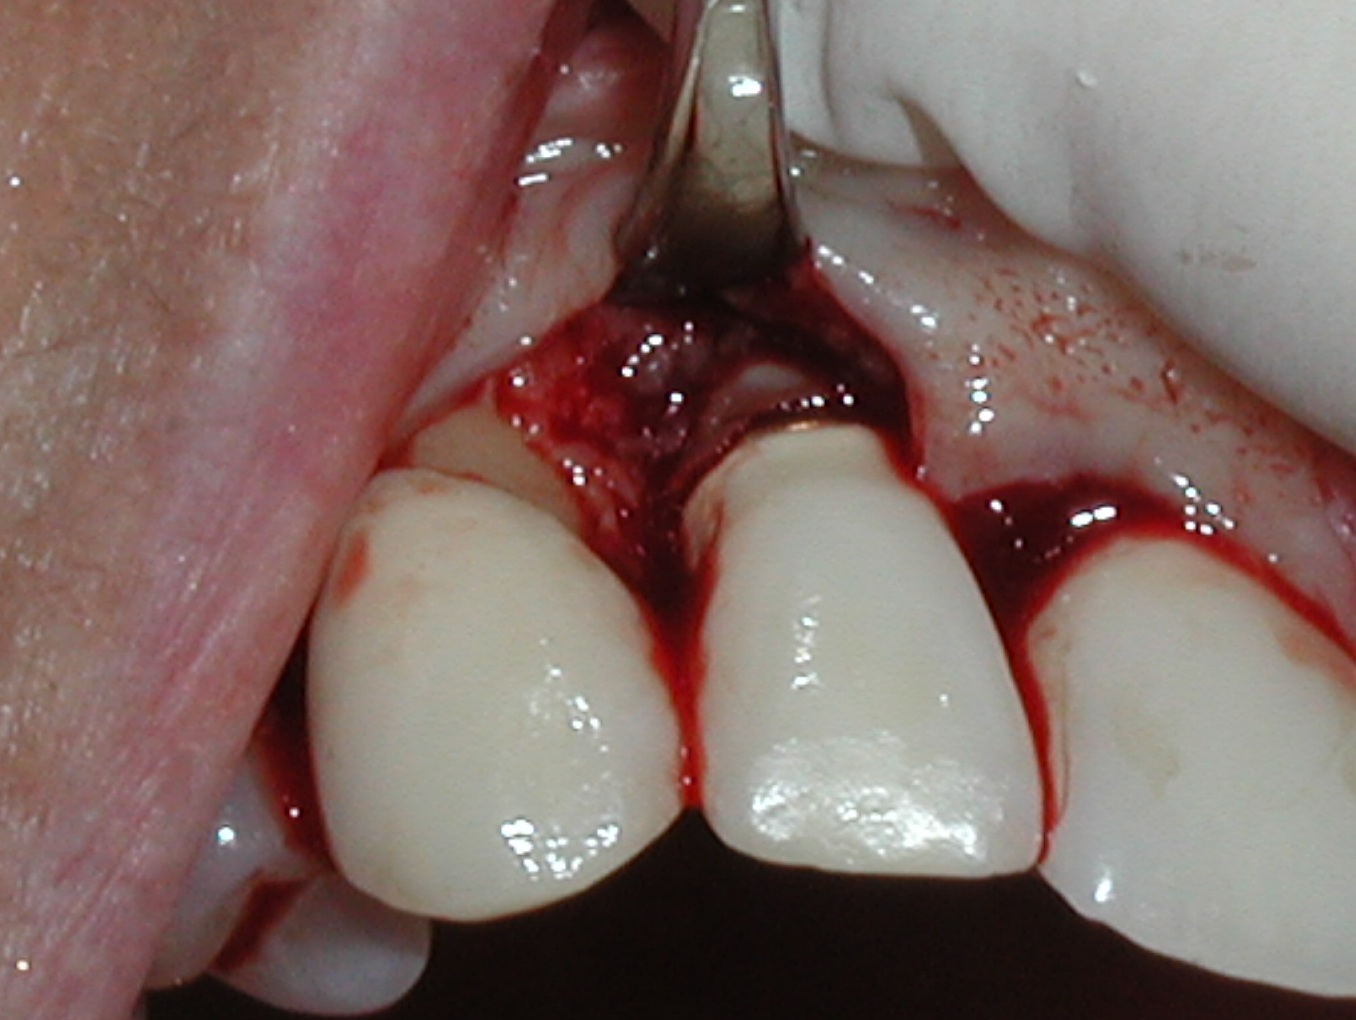

A guided bone regeneration (GBR) approach involving implant surface detoxification (Figure 2), placement of a bone graft combined with a barrier membrane (Figure 3 and Figure 4), and use of a systemic antibiotic has demonstrated the most predictable improvement in peri-implant parameters after destruction of supporting bone. GBR procedures demonstrated reductions in probing depth of 3.16 mm and 2.1 mm of radiographic bone fill in a recent systematic review and meta-analysis of 21 studies by Chan et al.21 Froum and Rosen22 defined a specific protocol based on reentry evaluation of previously treated peri-implantitis sites that included the use of rhPDGF-BB with freeze-dried mineralized bone and the addition of a resorbable membrane. Nonresorbable Gore-Tex® sutures were used to approximate the gingival tissue and were retained in place for 2 weeks. The patient was also kept on chlorhexidine for 2 weeks postoperatively. The reentry photographs from this report are quite impressive. However, the authors do caution the interpretation of re-osseointegration (Figure 5 and Figure 6).

Fig 3. A freeze-dried bone allograft was placed.

Figure 3

Fig 4. A resorbable collagen barrier was placed.

Figure 4